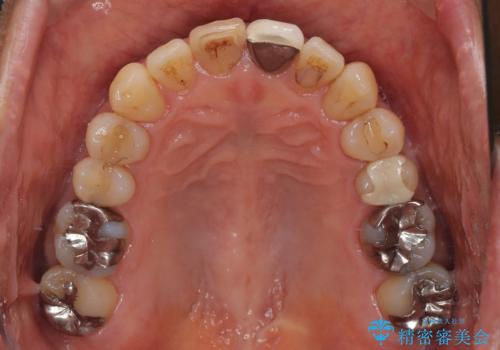

- 幼少期にぶつけてしまった前歯2本の変色を気にして来院された患者様です。

神経は生きているものの歯の色が茶色くなってきており、隣の歯は保険診療で装着したプラスチックのクラウンが徐々に黄ばんできている状態でした。

2本を同時にオールセラミッククラウンにて補綴治療を行うこととしました。